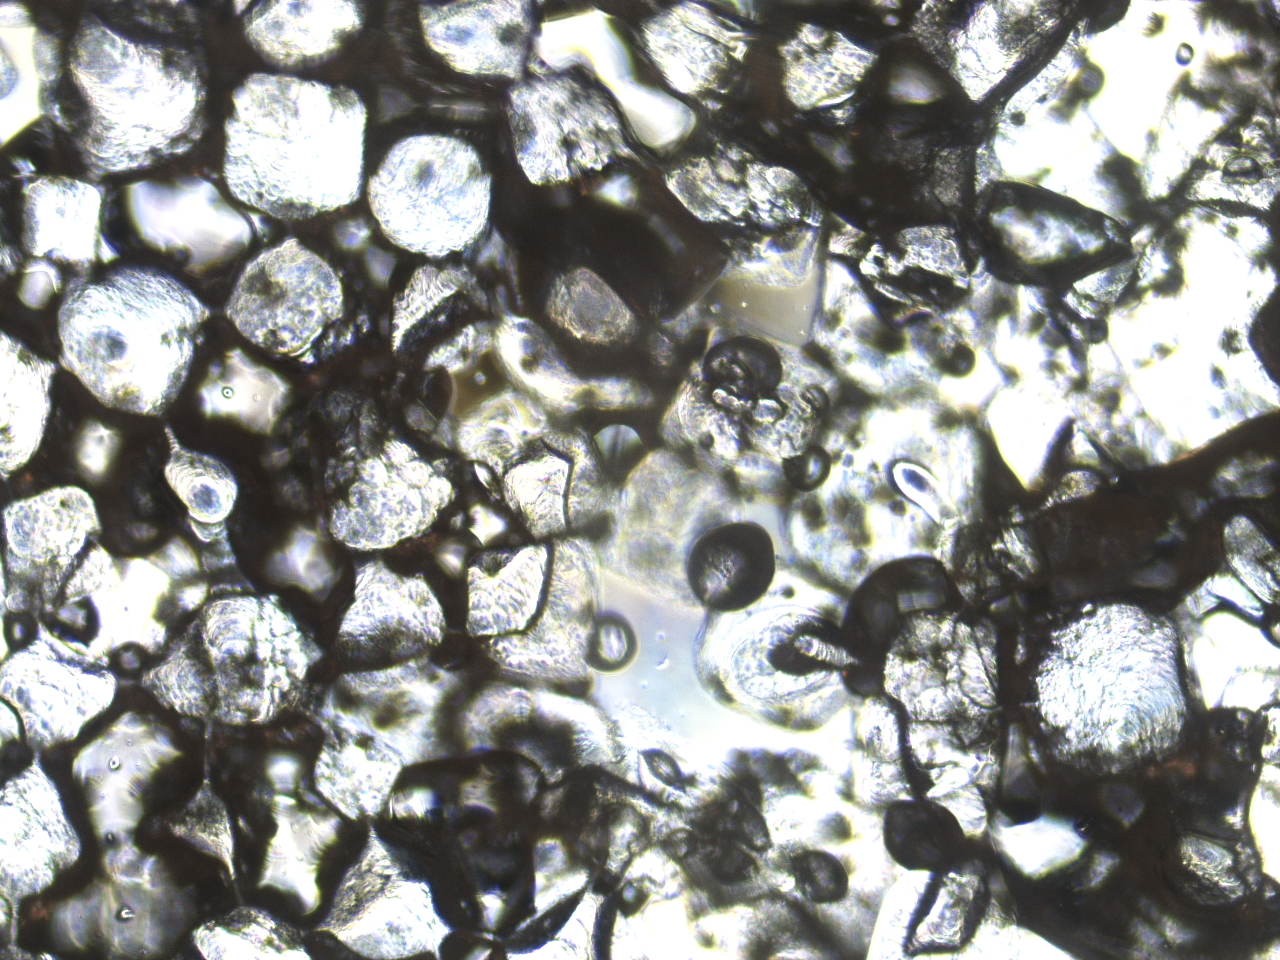

PLLA scaffolds for 3D Bone Tissue Engineering

Investigating the Effects of Mechanical Loading During Development in 3D Tissue-Engineered Bone

We report a novel, three-dimensional bone tissue model as a platform for musculoskeletal disease modeling that allows for compressive loading. By seeding induced pluripotent stem cell (iPSC) derived osteoblasts in a 3D, plasma treated, porous, gelatin coated, poly-L-lactide scaffold, we generated a 3D bone tissue culture with extracellular calcium deposition. By applying cyclical compression with an Arduino actuation device, we observed an improved bone phenotype. This method of generating 3D bone tissue may serve as a fast and accessible model for the formation of both healthy and pathological bone.

David Mack Lab at the Institute for Stem Cell and Regenerative Medicine